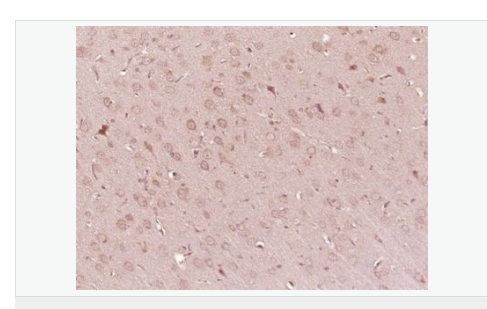

| 產(chǎn)品應用 | WB=1:500-2000 ELISA=1:5000-10000 IHC-P=1:100-500 IHC-F=1:100-500 IF=1:100-500 (石蠟切片需做抗原修復) not yet tested in other applications. optimal dilutions/concentrations should be determined by the end user. |